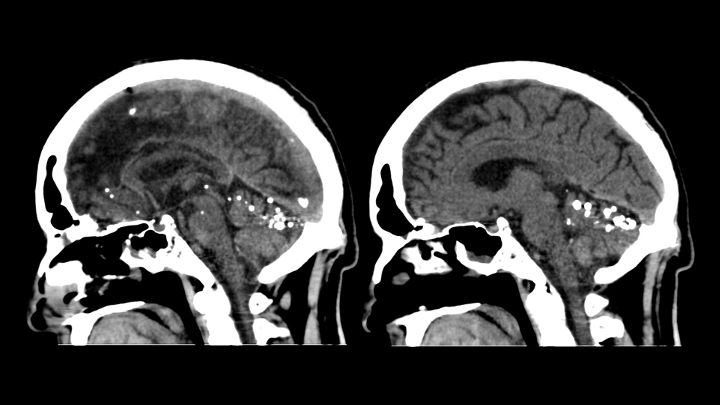

Se observan múltiples pequeños focos de material hiperatenuante dispersos en los espacios de circulación del LCR en la base del cráneo (localización extraaxial).

Se identifican múltiples pequeñas hiperdensidades intratecales, de tamaños variables.

El material presenta densidad metálica y genera artefactos en estría (streak artifacts).

El parénquima cerebral muestra cambios encefalomalácicos crónicos en territorio de la arteria cerebral media derecha, compatibles con secuela de infarto previo.